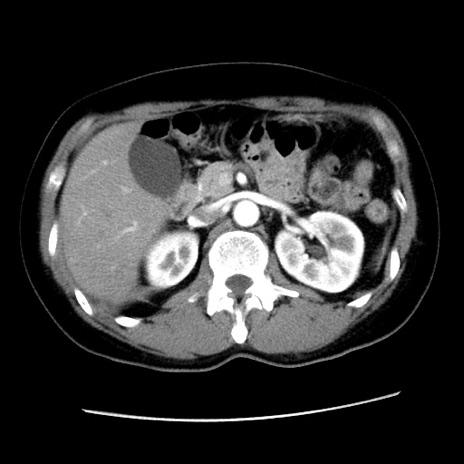

症例10(横断像)

【症例】 50歳代女性

【主訴】 腹痛

【現病歴】前日生レバーを食べた。今朝に排便あり。 昼前に突然発症の腹痛を生じ、当院救急外来を受診した。

【既往歴】 子宮筋腫にてで子宮全摘後

【身体所見】 意識清明、腹部:平坦、軟、下腹部やや左を中心に圧痛・反跳痛あり、筋性防御あり

【データ】WBC 7800、CRP 0.07